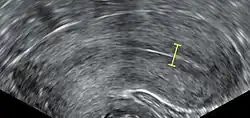

The endometrium is the innermost lining layer of the uterus, and functions to prevent adhesions between the opposed walls of the myometrium, thereby maintaining the patency of the uterine cavity.[12] During the menstrual cycle or estrous cycle, the endometrium grows to a thick, blood vessel-rich, glandular tissue layer. This represents an optimal environment for the implantation of a blastocyst upon its arrival in the uterus. The endometrium is central, echogenic (detectable using ultrasound scanners), and has an average thickness of 6.7 mm.

An endometrial thickness (EMT) of less than 7 mm decreases the pregnancy rate in in vitro fertilization by an odds ratio of approximately 0.4 compared to an EMT of over 7 mm. However, such low thickness rarely occurs, and any routine use of this parameter is regarded as not justified. The optimal endometrial thickness is 10mm. Nevertheless, in human a perfect synchrony is not necessary; if the endometrium is not ready to receive the embryo an ectopic pregnancy may occur. This consist of the implantation of the blast outside the uterus, which can be extremely dangerous.[20]

Observation of the endometrium by transvaginal ultrasonography is used when administering fertility medication, such as in in vitro fertilization. At the time of embryo transfer, it is favorable to have an endometrium of a thickness of between 7 and 14 mm with a triple-line configuration,[21] which means that the endometrium contains a hyperechoic (usually displayed as light) line in the middle surrounded by two more hypoechoic (darker) lines. A triple-line endometrium reflects the separation of the basal layer and the functional layer, and is also observed in the periovulatory period secondary to rising estradiol levels, and disappears after ovulation.[22]

Endometrial thickness is also associated with live births in IVF. The live birth rate in a normal endometrium is halved when the thickness is <5mm.[23]